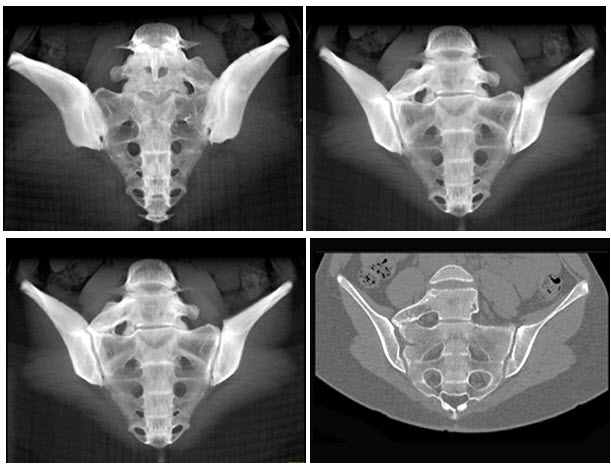

8、单项选择题

男,13岁,右髋部疼痛不适,无红肿,结合所提供的图像,最可能的诊断是()

A.非骨化性纤维瘤

B.骨巨细胞瘤

C.畸形性骨炎

D.内生软骨瘤

E.骨纤维结构不良

33、单项选择题

男,53岁,腰骶部持续性隐痛,可扪及肿大包块3月余,结合影像学检查,最可能的诊断是()

A.骨巨细胞瘤

B.骨肉瘤

C.骨囊肿

D.脊索瘤

E.骨脓肿

女,49岁,骶部隐痛1月余,结合影像学检查,最可能的诊断是()

A.脊索瘤

B.骨转移瘤

C.骨巨细胞瘤

D.骨囊肿

E.骨结核

男,59岁,右侧髋骶部持续性疼痛,夜间加重,2月前被确诊为肾细胞癌,结合图像,最可能的诊断是()

A.骨肉瘤

D.骨转移瘤

E.骨瘤

120、单项选择题

男,56岁,肺癌术后2年余,左髋部疼痛,夜间加重,结合图像,最可能的诊断是()

B.骨转移

C.多发性骨髓瘤

D.骨软骨瘤

E.软骨肉瘤